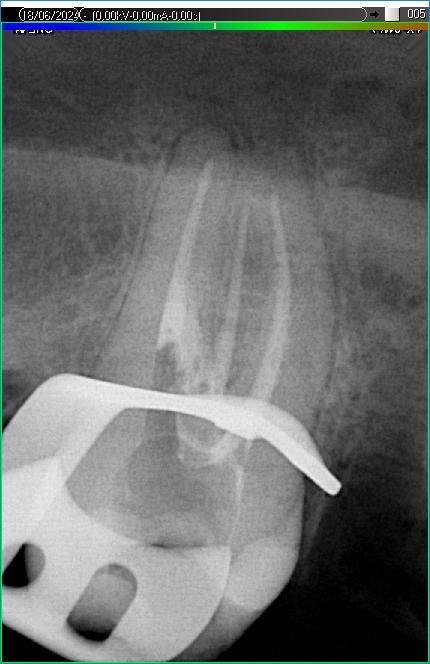

Вилучення інструменту з каналів зуба